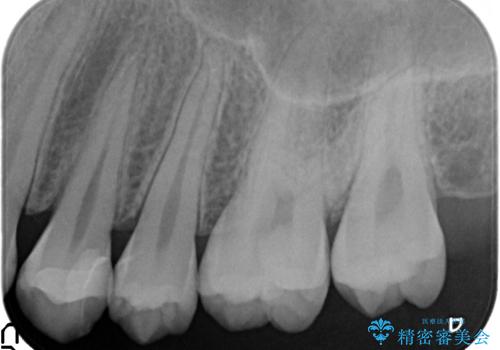

- 左上4番目の歯が欠けてしまったので診て欲しいといらっしゃった方の症例です。

白い詰め物を御希望されたので、セラミックインレーによる修復を行いました。

当院のセラミックインレーはemaxという強度と審美性に優れた材料を使用しています。

またプレス方式でインレーを製作しているため、削り出しで製作するCADCAMより優れた適合性も持ち合わせており、虫歯が再発しにくい修復物です。